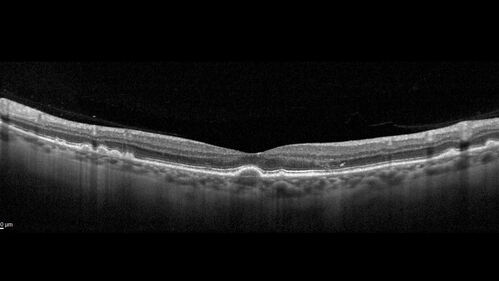

Dry AMD - Pigment - AREDS risk score of 4

65 year old woman with 20/32 vision. A little blurred. Pigment and large drusen in each eye. AREDS risk score of four.